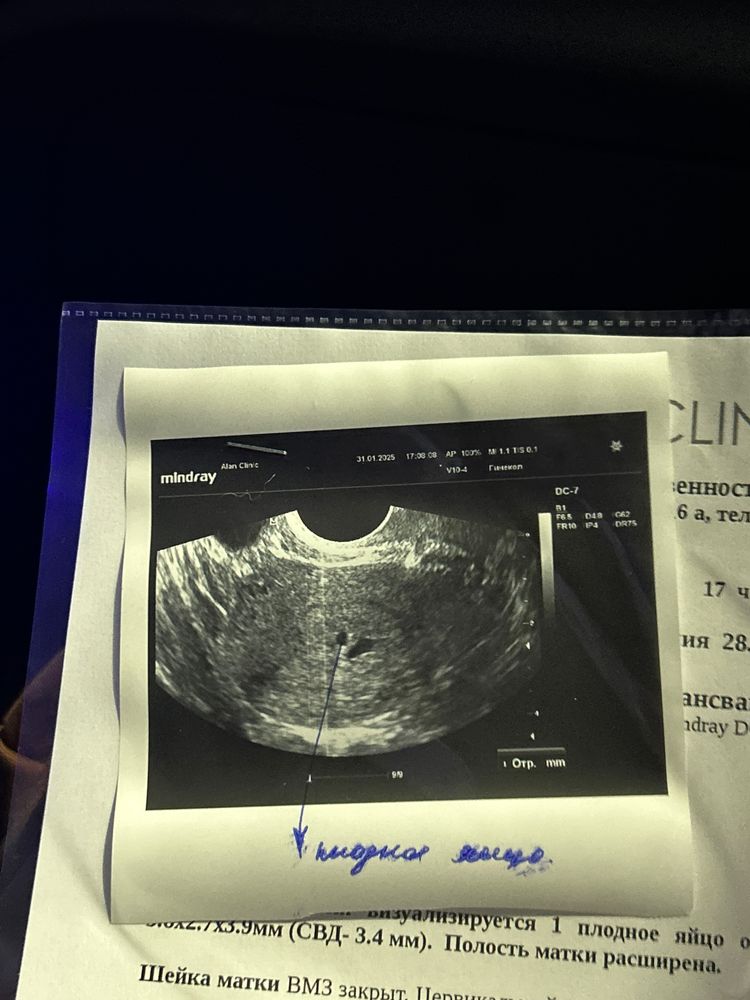

8 недель, самочувствие Второе УЗИ ❤️